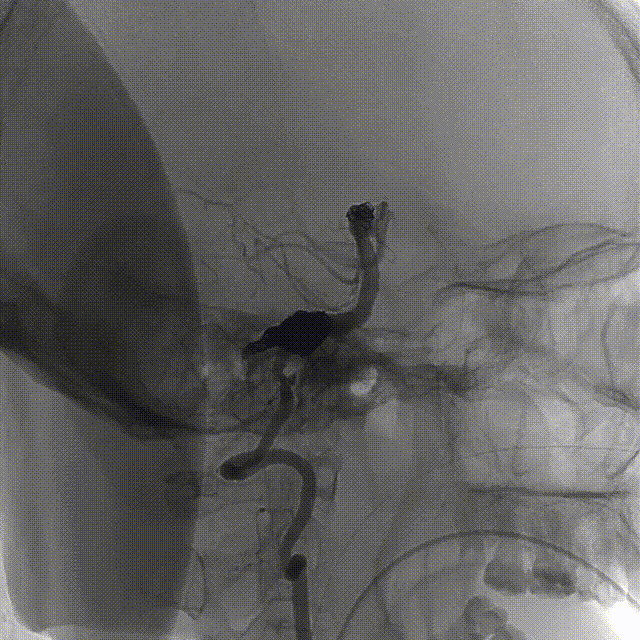

图3. 双侧颈总动脉造影:A和B为右侧颈总动脉造影提示颈内动脉颅内段迂曲,后交通动脉开放;C和D为左侧颈总动脉造影也可见颈内动脉迂曲,后交通动脉开放供应同侧大脑后动脉。